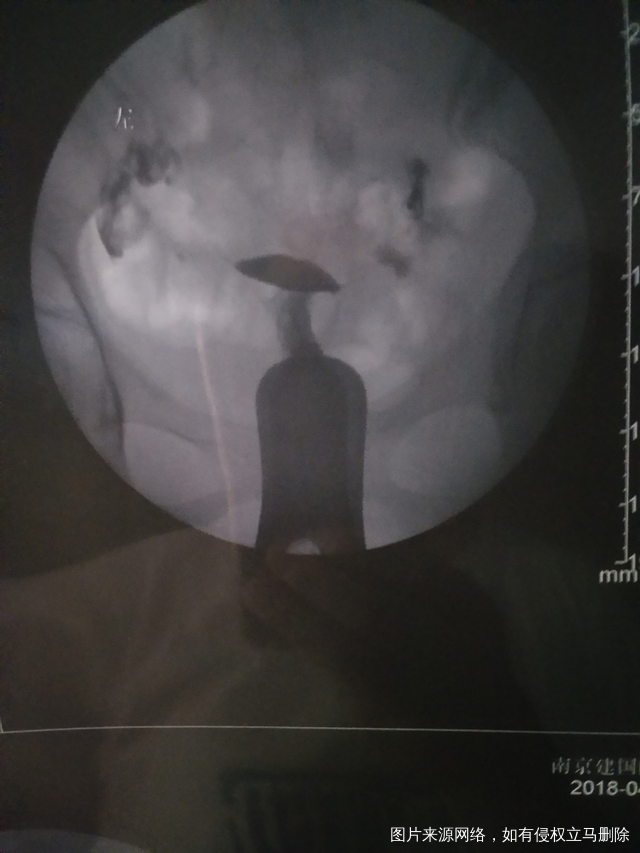

医生再帮我看看通吗她下面写双侧大该通还是就不通